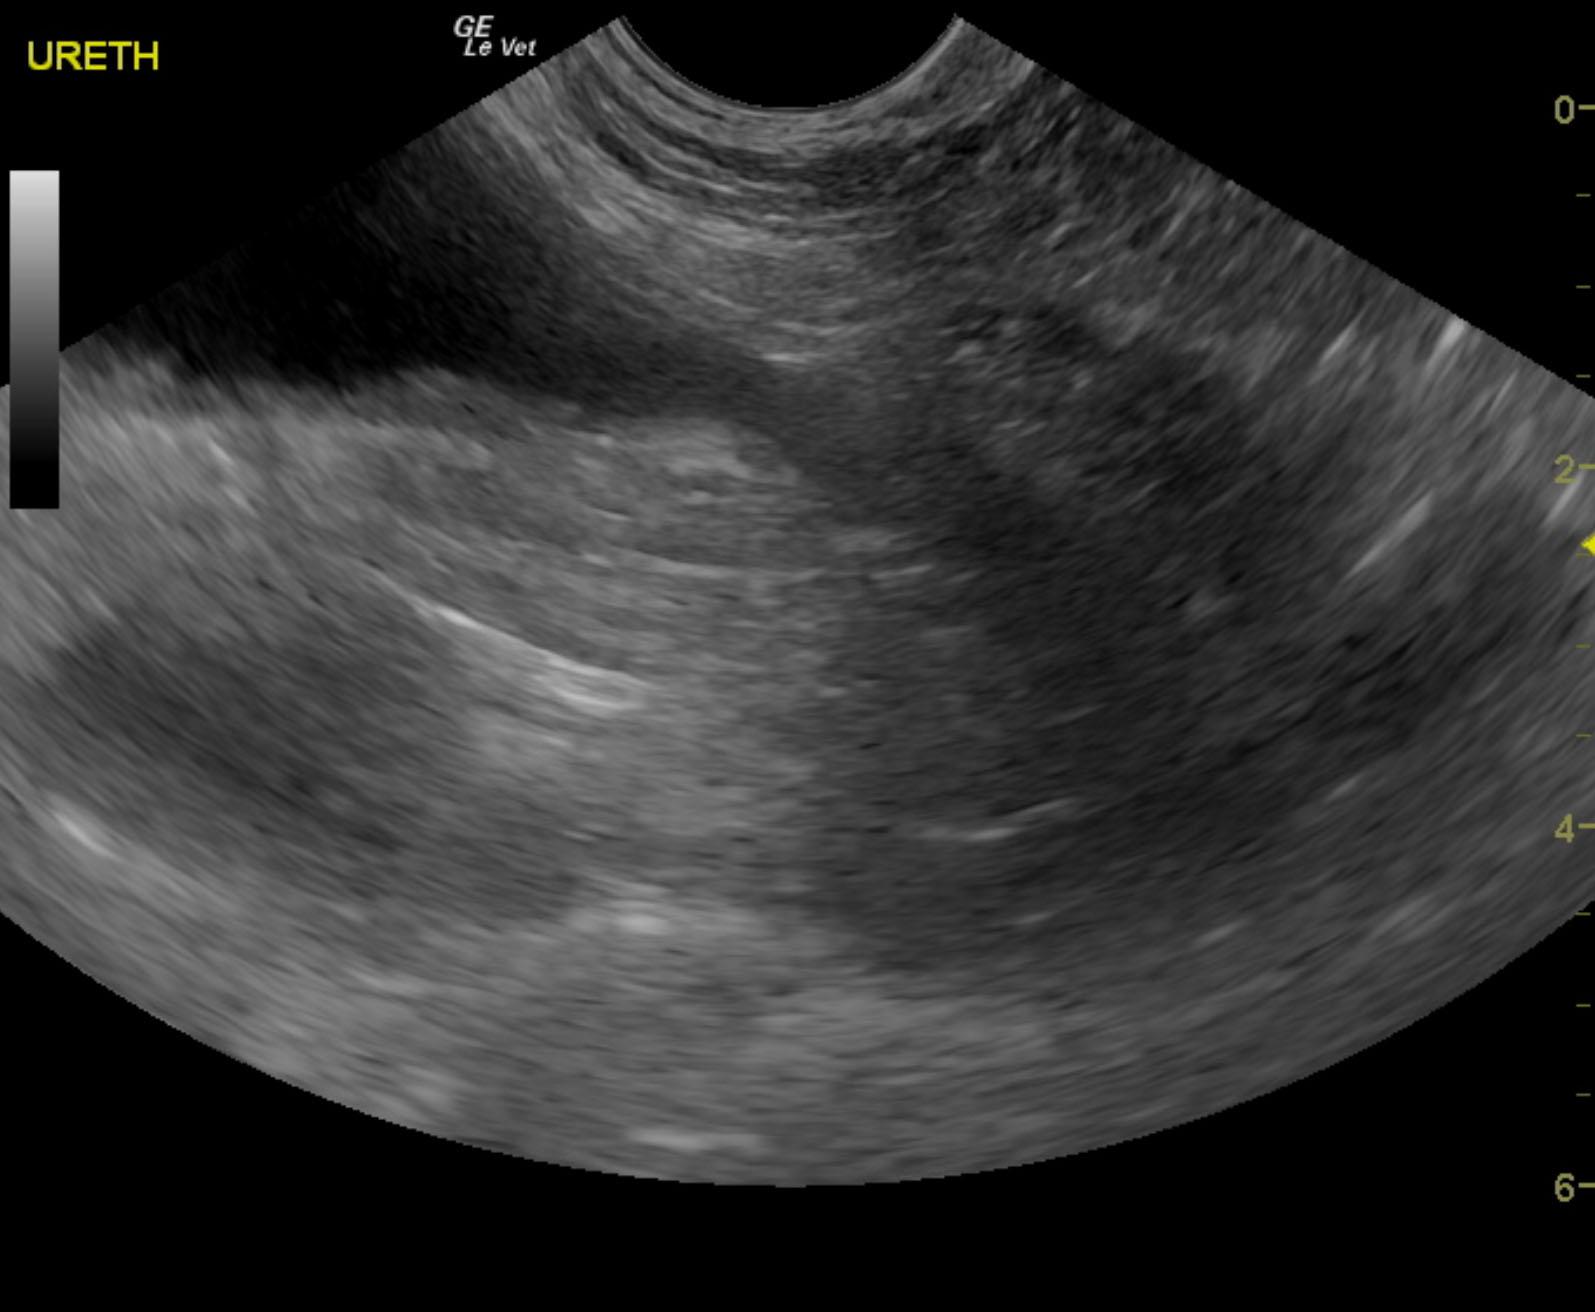

A 9-year-old spayed female Welsh Corgi dog was presented for evaluation for recurrent hematuria. On urinalysis, inappropriate SG (1.020) and proteinuria were present. Urine culture revealed Acinetobacter, Pseudomonas, and Enterobacter; the latter two were antibiotic resistant strains.